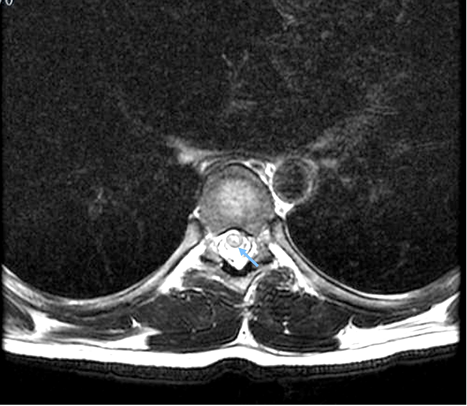

Due to early vesical incontinence, magnetic resonance imaging of the thoracolumbar spine was performed, which showed an alteration in the intensity of the spinal cord observed from the T2 level to the conus medullaris, which initiates in the anterior horns and then generalizes throughout the circumference of the spinal cord with significant thickening. These findings were consistent with longitudinally extensive transverse inflammatory myelopathy (Figure 1, 2, and 3).

Figure 2. Sequence T2